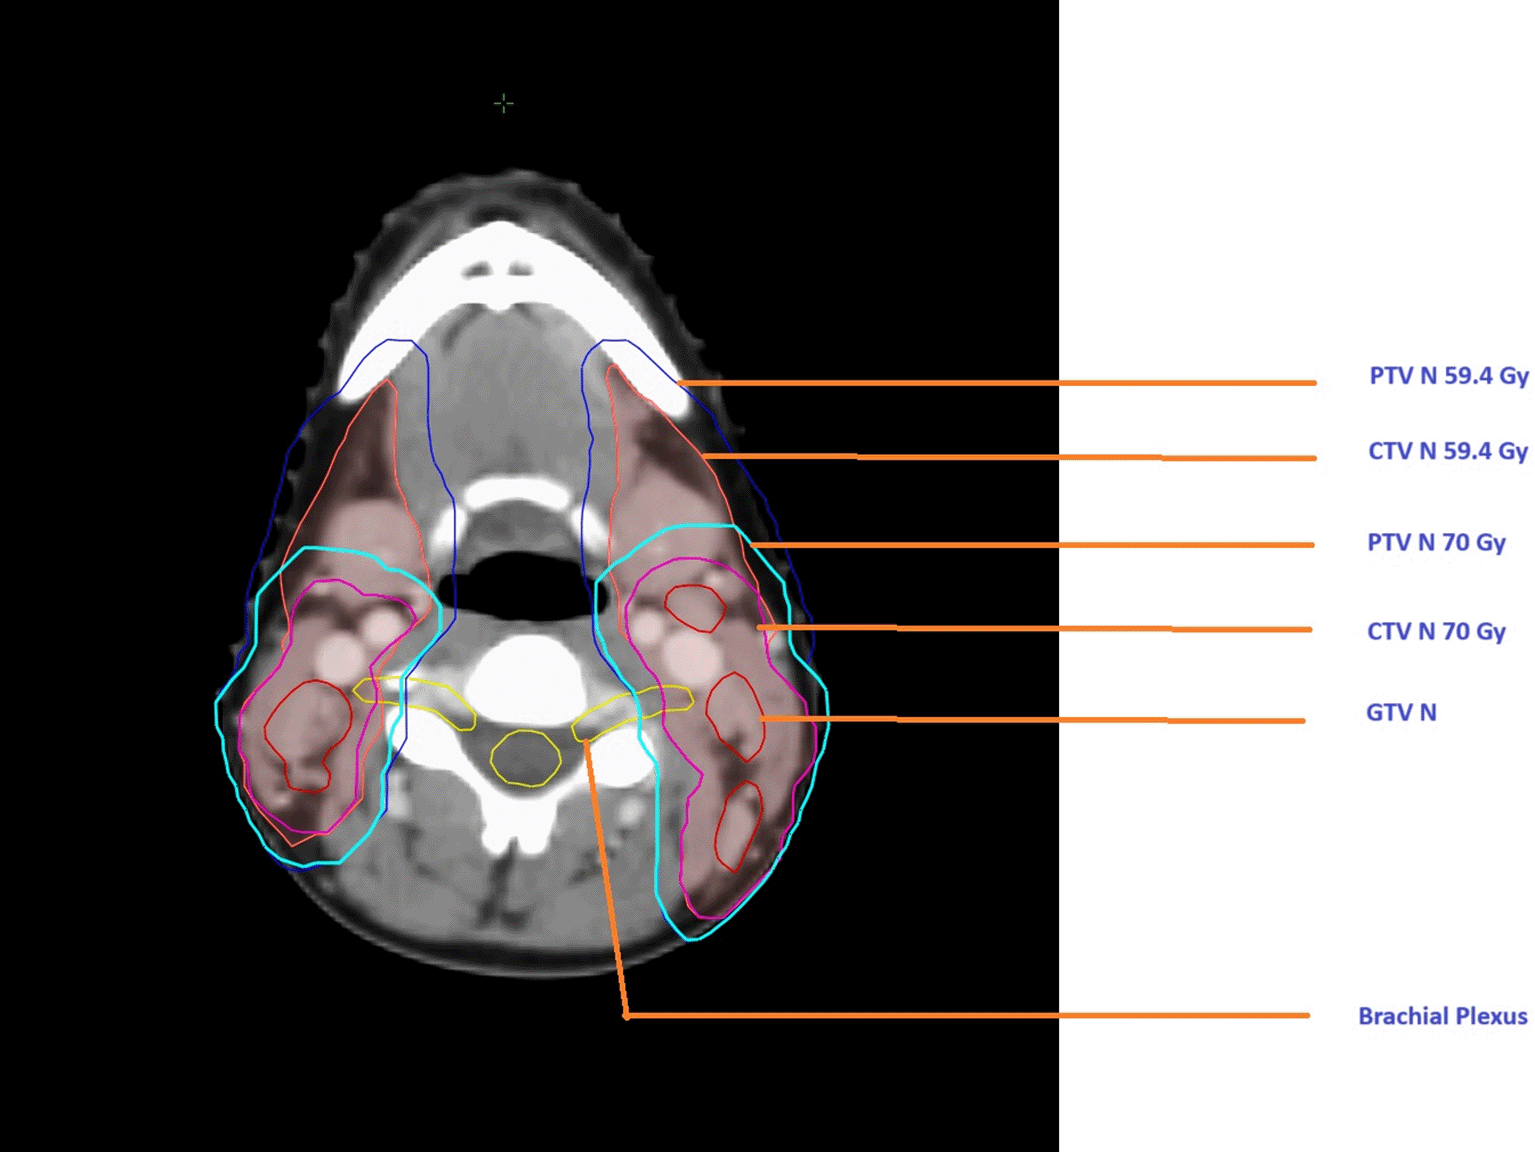

Imaging for treatment planning was conducted using a Philips® BigBore simulator scanner with 3 mm slice thickness. Patients were positioned supine, immobilized with a 5-point thermoplastic mask, and underwent a dosimetric scan with intravenous contrast when there were no contraindications. Target volumes were defined according to ICRU guidelines,14,15 with three key volumes: Gross Tumor Volume (GTV), Clinical Target Volume (CTV), and Planning Target Volume (PTV) (Figure 1). The GTV includes visible tumor, the CTV encompasses areas with potential microscopic disease, and the PTV adds a margin to account for uncertainties such as patient motion and setup errors. High-risk CTVs receive the highest dose, extending from the GTV to include the nasopharyngeal region, with margins depending on anatomical boundaries and nodal involvement.16,17 Intermediate- and low-risk CTVs are defined based on the tumor’s extension and regional lymph node involvement. The PTV was defined by extending the CTV by 5 mm in all directions to account for treatment uncertainties. This margin was applied to both the nasopharyngeal and lymph node regions (Figure 1). In our study, the brachial plexus was delineated following the Radiation Therapy Oncology Group (RTOG 618) guidelines, with contouring adjustments at the lower part based on the recommendations of Sun Ki Yi et al. This adjustment was necessary due to the requirement to irradiate the level 4 lymph node area within the prophylactic volume18,19 (Figure 2). The treatment was administered using a linear accelerator with the IMRT technique (VARIAN CLINAC® IX, MLC 120) and 6 MV X-rays (Figure 3). All patients received 2 Gy per session, five days a week, targeting the tumor volume and affected lymph nodes, totaling 70 Gy. For intermediate-risk cervical lymph node areas (retropharyngeal, II, III, V, and occasionally IV, Ia, Ib according to N involvement), the prescribed dose was 59.4 Gy with 1.7 Gy per fraction across 35 sessions in simultaneous integrated boost.

25d45b26-5387-42c6-94b5-f7b7a30f5503_figure1.gif

Figure 1. Target volume delineation.